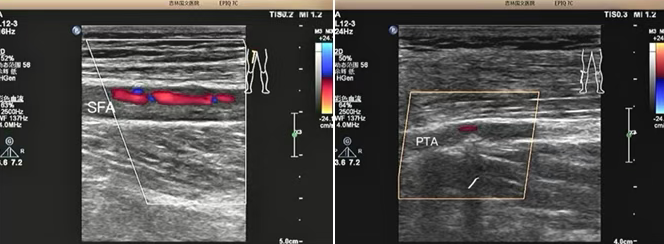

該患者是一位老年男性,因 “雙小腿麻木、發(fā)涼 2 個(gè)月” 前來我院就診。超聲科為其進(jìn)行下肢動(dòng)靜脈彩超檢查時(shí),精準(zhǔn)發(fā)現(xiàn)其股淺動(dòng)脈及脛后動(dòng)脈存在重度狹窄至閉塞的情況。超聲檢查憑借其無創(chuàng)、便捷的獨(dú)特優(yōu)勢(shì),在第一時(shí)間就為臨床治療提供了準(zhǔn)確無誤的診斷依據(jù),為后續(xù)治療方案的制定奠定了堅(jiān)實(shí)基礎(chǔ)。

超聲檢查以其無創(chuàng)、便捷、可重復(fù)的顯著優(yōu)勢(shì),在此次診療過程中發(fā)揮了重要作用,清晰地顯示了患者下肢動(dòng)脈的病變情況:1、準(zhǔn)確判斷病變部位:精準(zhǔn)定位到股淺動(dòng)脈及脛后動(dòng)脈。2、明確病變程度:確定為重度狹窄至閉塞。3、評(píng)估側(cè)支循環(huán)建立情況:為治療方案的制定提供了關(guān)鍵參考。